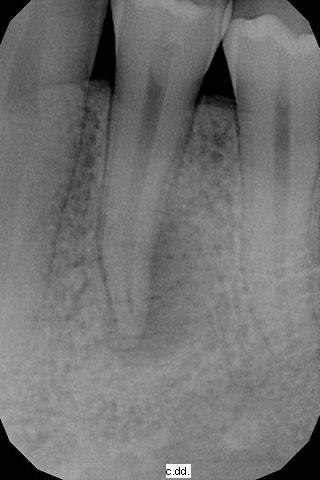

La paziente si presenta per un problema al 34. Presenza di dolore alla masticazione, sensazione di dente allungato, il test pulpare è positivo, dolore alla percussione e alla palpazione, assenza di mobilità dentale. L' rx endorale conferma la presenza di una lesione apicale acuta ipotizzata all'esame clnico. La terapia è endodontica.